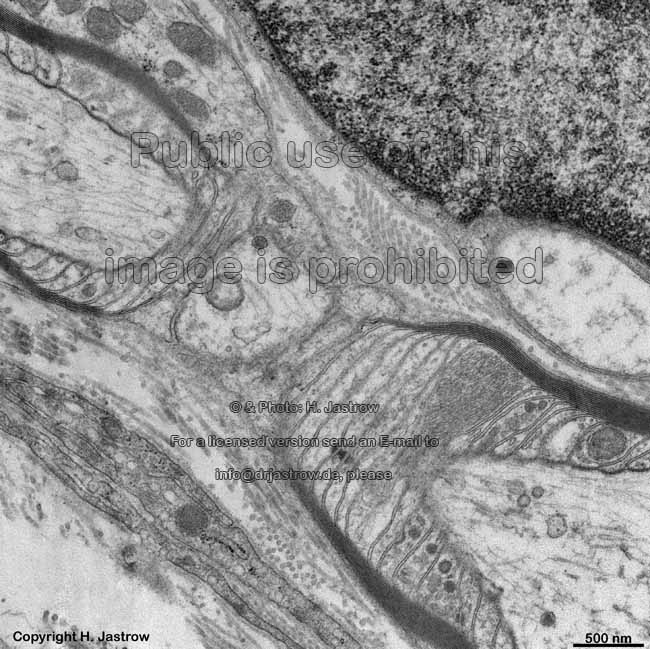

node of Ranvier in longi-

tudinal section (monkey)

idem + Schmidt-Lanter-

man incisure (monkey)

tudinal detail (monkey)